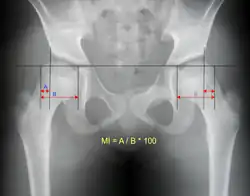

Reimer's migration index can be used to indicate hip dislocation. The migration index (MI) is normally less than 33%.[23]